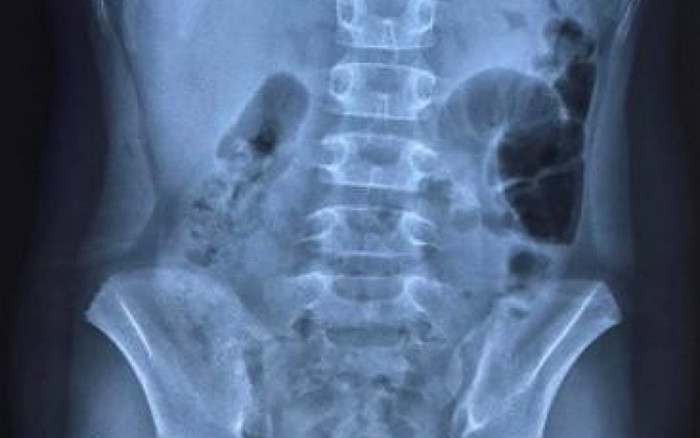

Hình ảnh chụp X-Quang bệnh nhi thể hiện liềm hơi dưới vòm hoành 2 bên, dấu hiệu chẩn đoán thủng tạng rỗng. Ảnh: Bệnh viện Trẻ em Hải Phòng.

Theo hình ảnh chụp X-quang, bệnh nhi có liềm hơi dưới vòm hoành 2 bên. Bé được chẩn đoán bị viêm phúc mạc do thủng dạ dày/mắc Covid-19.